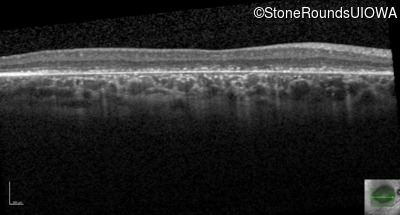

Age at visit: 6 years

OD OS

Age at visit: 5 years

Age at visit: 7 years

Age at visit: 8 years

Age at visit: 9 years

Age at visit: 11 years

Age at visit: 12 years

Age at visit: 13 years

Age at visit: 14 years

Age at visit: 17 years